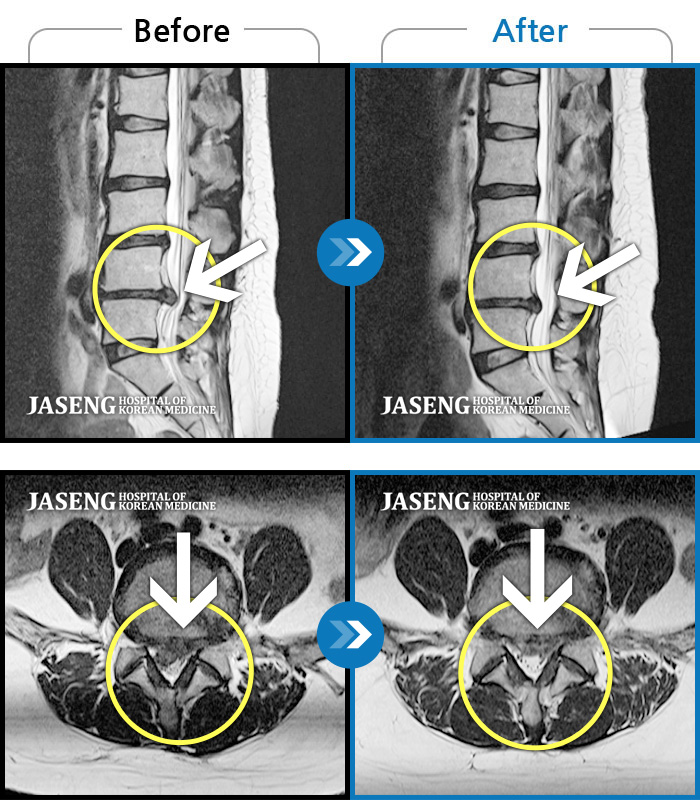

Before

After

환자에게 사전 동의를 받아 동일 조건에서 촬영되었습니다.

개인에 따라 치료 후 부작용이 발생할 수 있으니 의료진과 상담 후 치료를 진행하시기 바랍니다.

허리 통증과 왼쪽 골반에서 종아리까지 당기는 통증

허리 뻐근한 통증과 왼쪽 종아리 저림